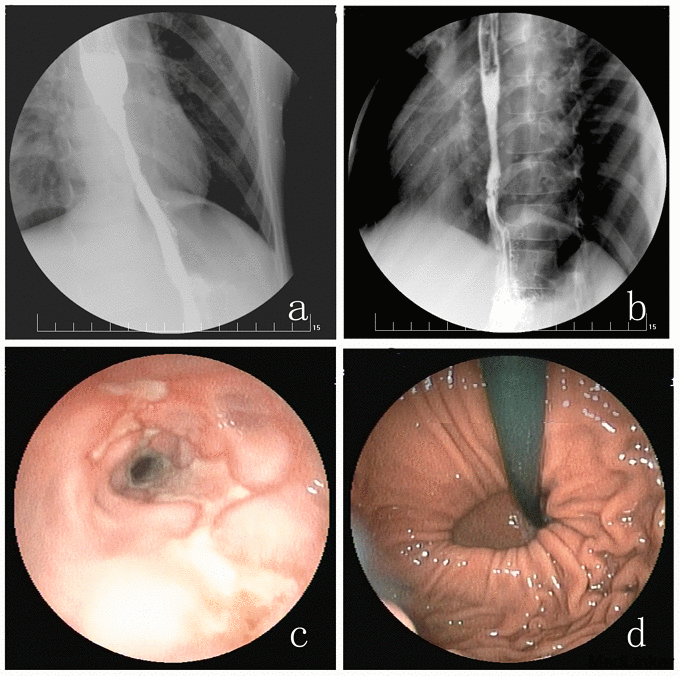

上消化道造影示:食管下段欠顺畅,管腔狭窄,见图1a、1b;胃-食管钡剂少量反流。纤维胃镜检查报告示:反流性食管炎(LA-D级);下段食管溃疡(A1期),伴假憩室形成;食管裂孔疝(图1c、1d)。入院诊断:GERD,反流性食管炎(LA-D级),PES,食管裂孔疝。